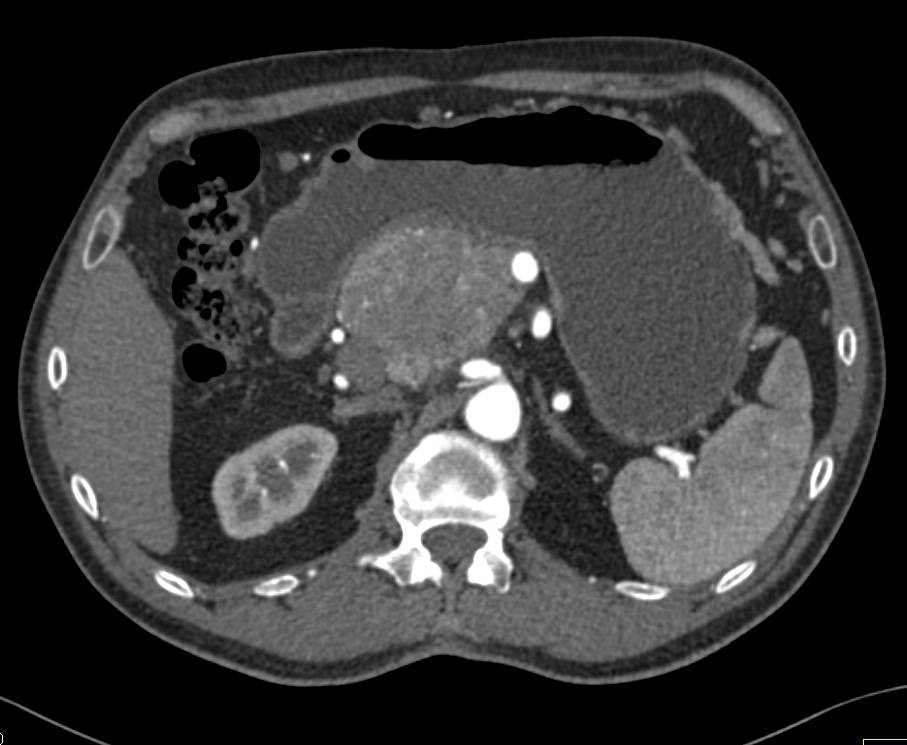

Neuroendocrine Tumor in the Head of the Pancreas